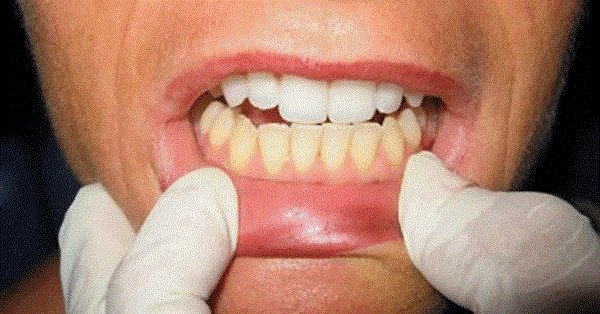

Gjëja e parë që vërejmë te një njeri kur flasim janë dhëmbët. Të kesh dhëmbë të bukur dhe të bardhë është perfekte dhe do shumë punë që ti mbash.

Boronicat nuk ndikojnë negativisht në shëndetin e dhëmbëve, por i ngjyrosin dhëmbët me ngjyrë të kaltër. Stomatologët këshillojnë të mos i konsumoni shpesh boronicat dhe në këtë mënyrë do të shmangni ngjyrimin e tyre. Personat që i konsumojnë shpesh boronicat kanë dhëmbë të verdhë.